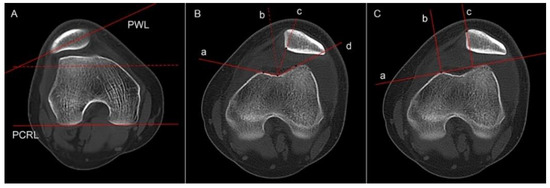

2.3.2. Tibial Tubercle Lateralization